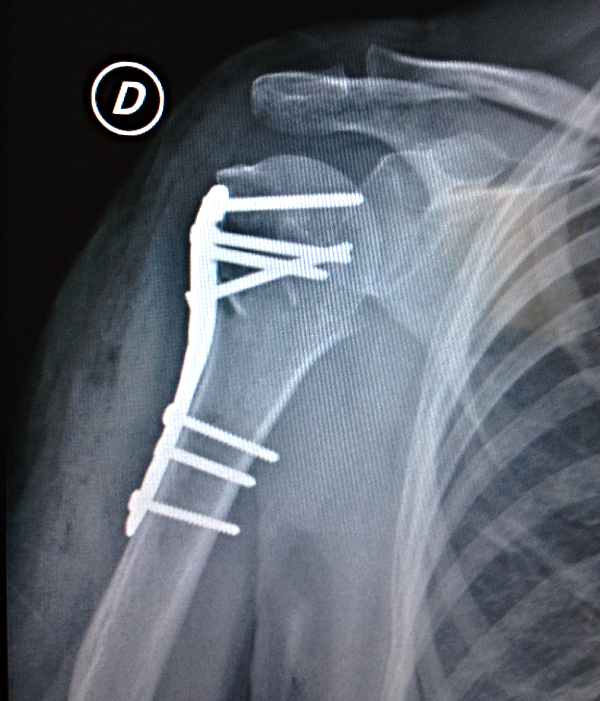

Fractura de Húmero próximal | Osteosíntesis

Las fracturas del húmero próximal, se presentan generalmente en personas con osteoporosis en la edad adulta, y por traumatismos de alta energía en personas jovenes, el tratamiento puede ser desde conservador o quirúrgico mediante osteosíntesis o fijadores externos, dependiendo de las caracteristicas del paciente.